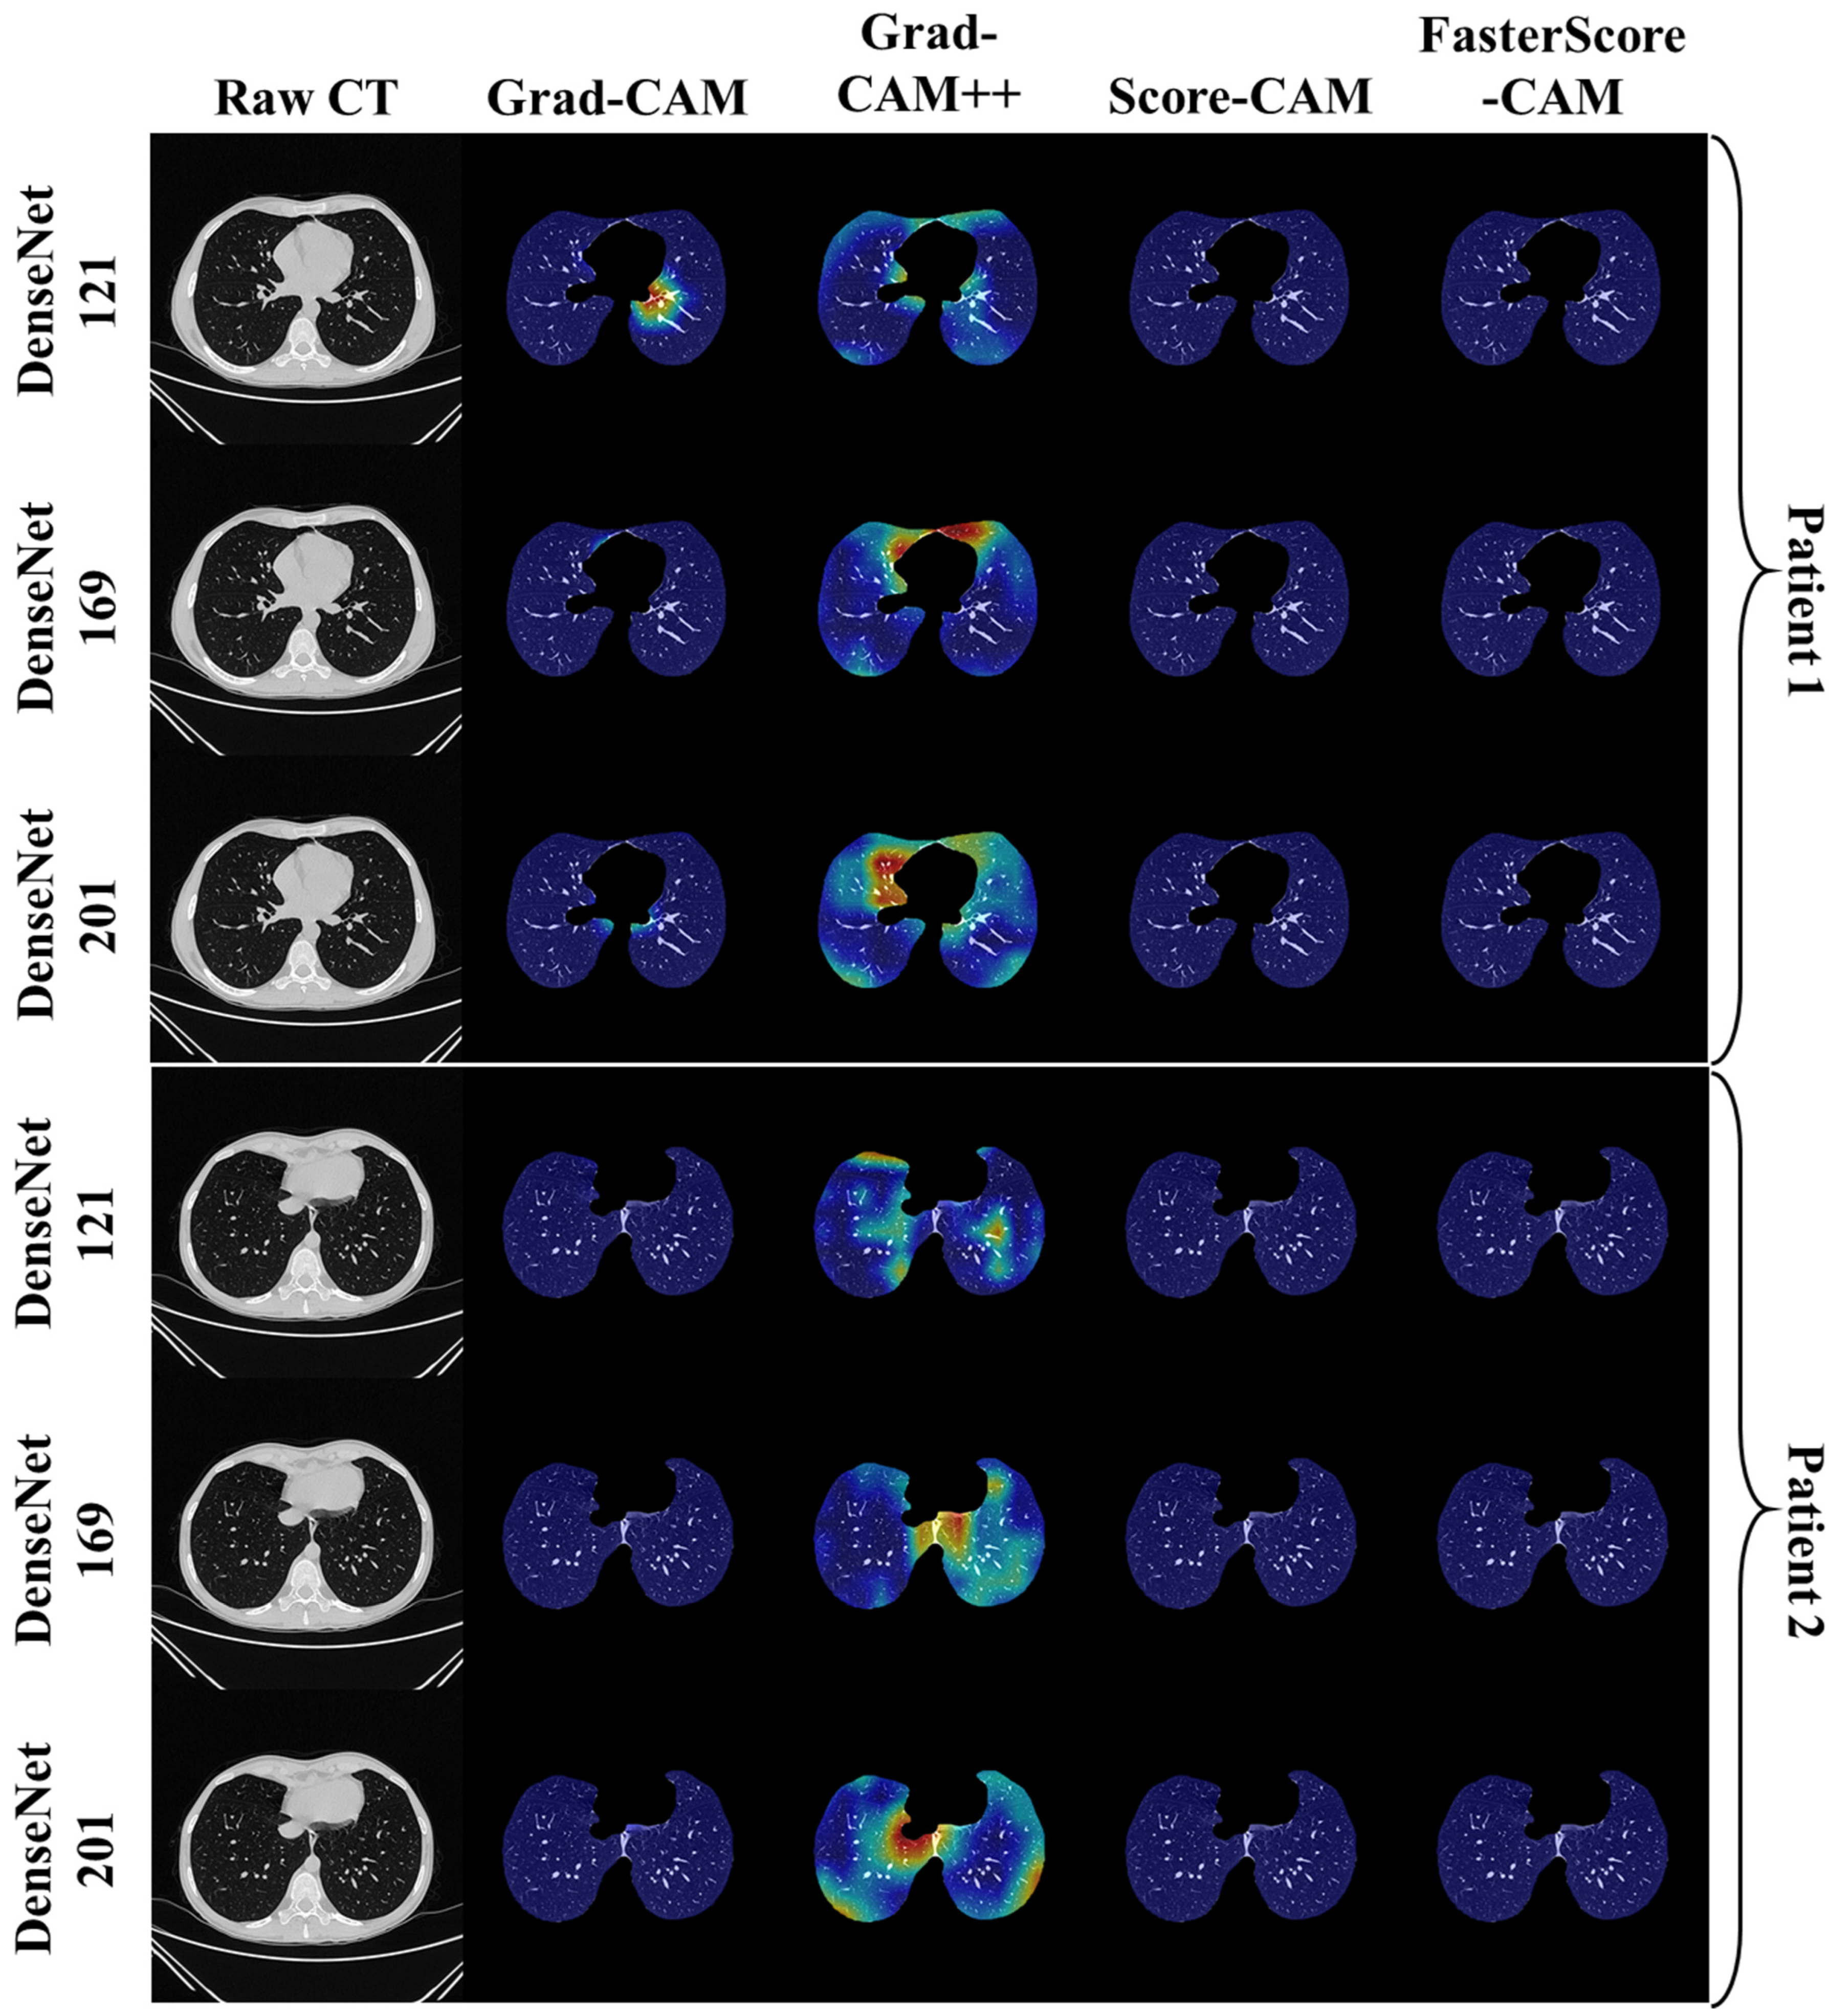

Visual Results Representing Lesion Using the Four CAM Techniques

4.1. Study Findings

4.4. A Special Note on Four CAM Models